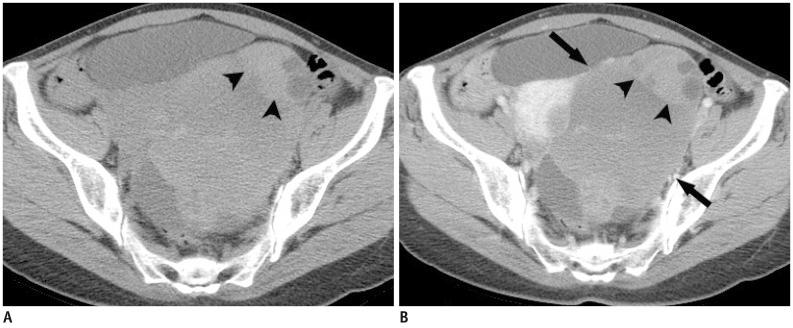

多排螺旋 CT 在附件包块评估中的应用:平扫 CT 是否有必要?

Multidetector computed tomography for the assessment of adnexal mass: is unenhanced CT scan necessary?

To compare the diagnostic performance and radiation dose between contrast-enhanced CT (ECT) alone, and combined unenhanced and contrast-enhanced CT (UE + ECT) for the assessment of adnexal mass.

比较单独对比增强 CT(ECT)与联合平扫和增强 CT(UE + ECT)在评估附件肿块中的诊断性能和辐射剂量。